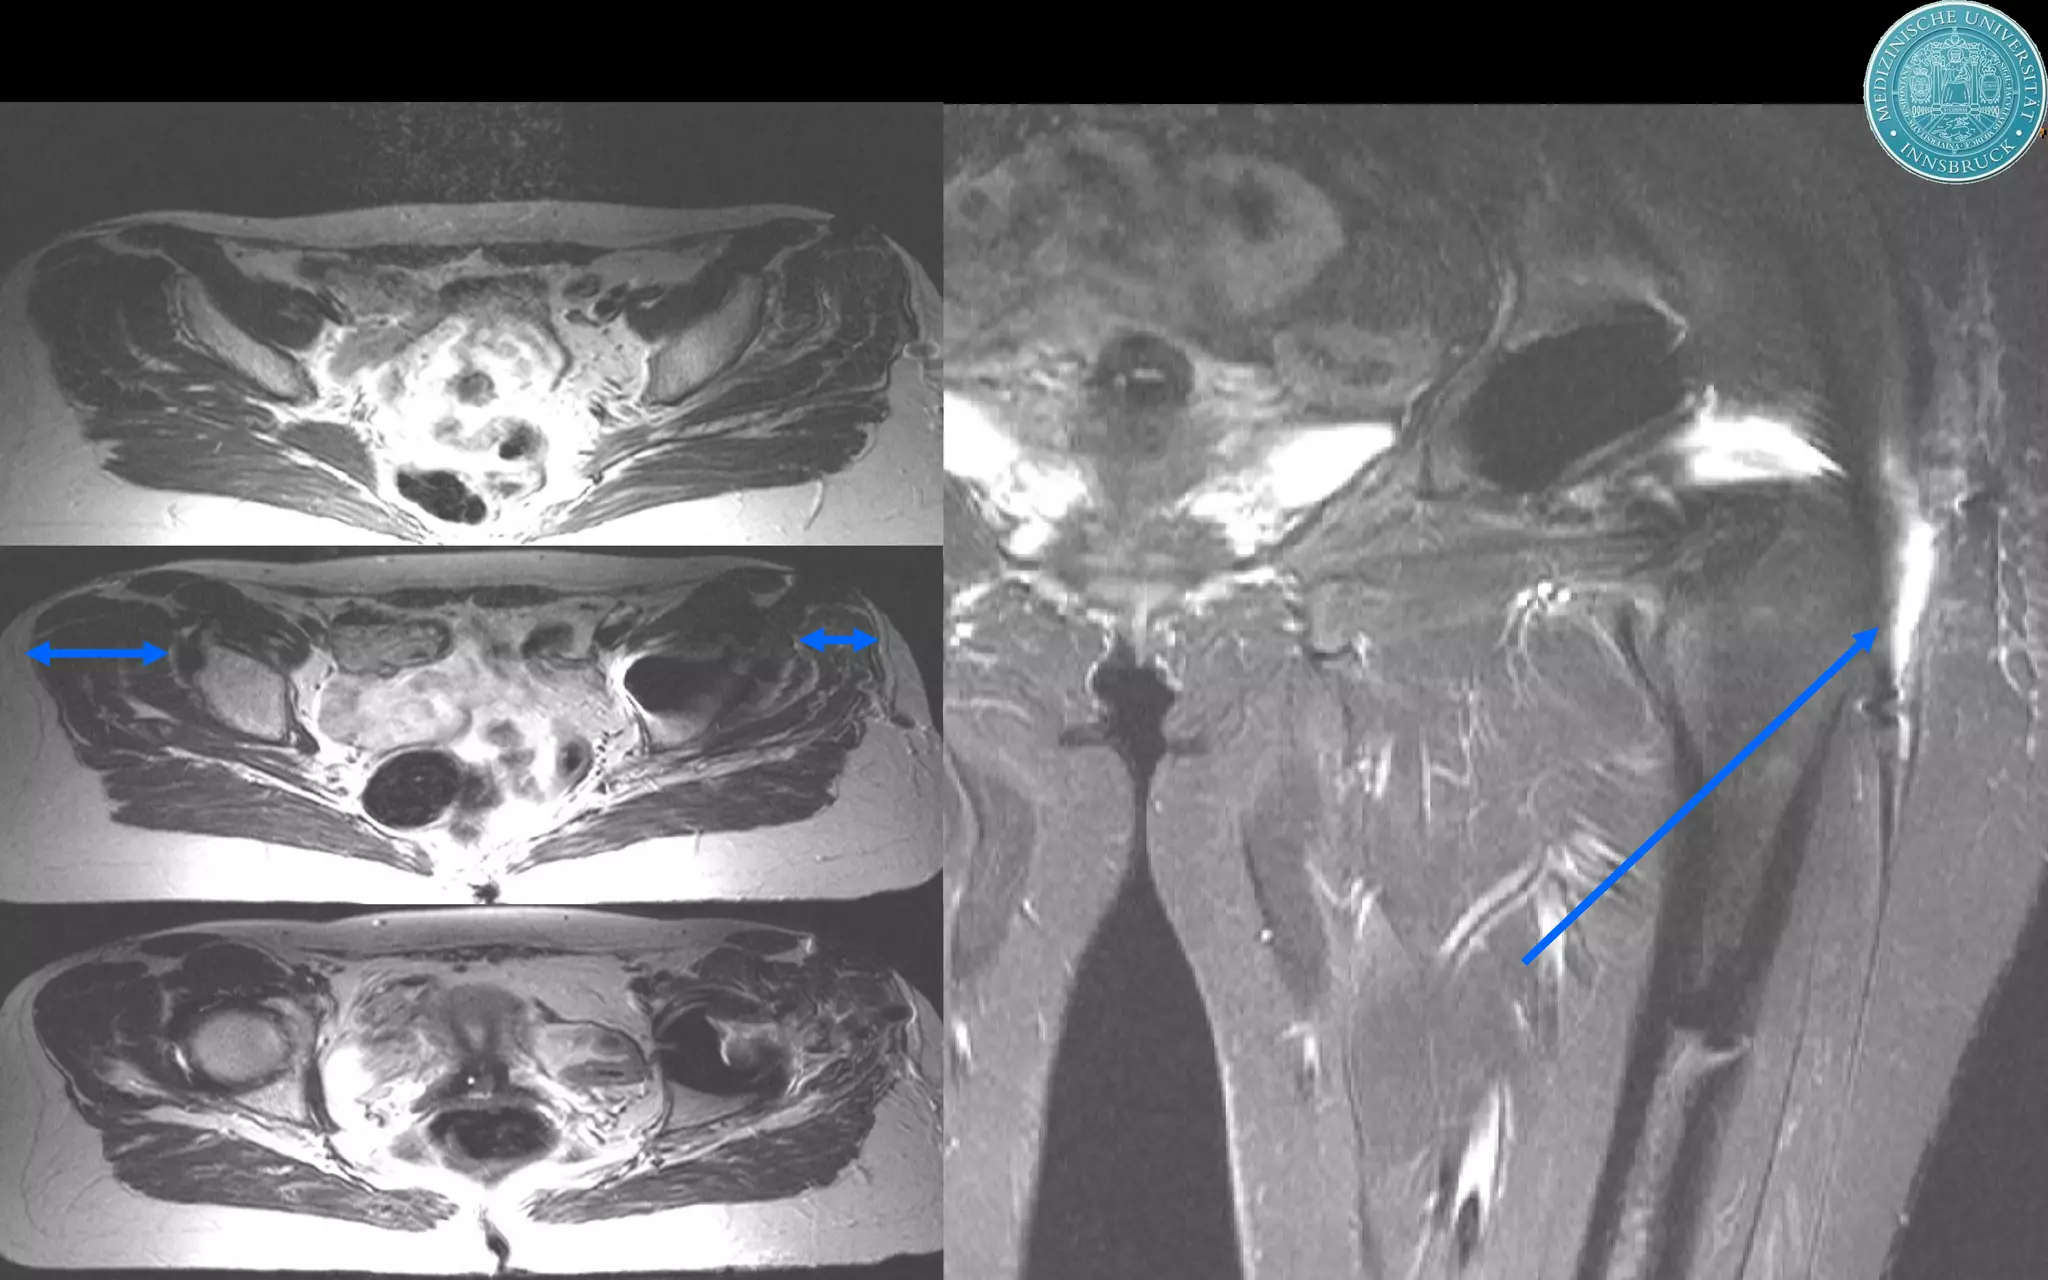

This document discusses the direct anterior approach for total hip arthroplasty. It lists advantages of the direct anterior approach such as increased stability, easier leg length equalization, lower costs by not requiring an operating table, reduced radiation exposure, faster rehabilitation, and lower risk of deep vein thrombosis. The document also discusses the historical background of the direct anterior approach, showing it has been performed since the 1880s. It presents images showing fatty degeneration of muscles and gluteal atrophy after total hip arthroplasty. Finally, it displays graphs comparing outcomes and improvements in quality of life domains between the direct anterior approach and minimally invasive approaches.